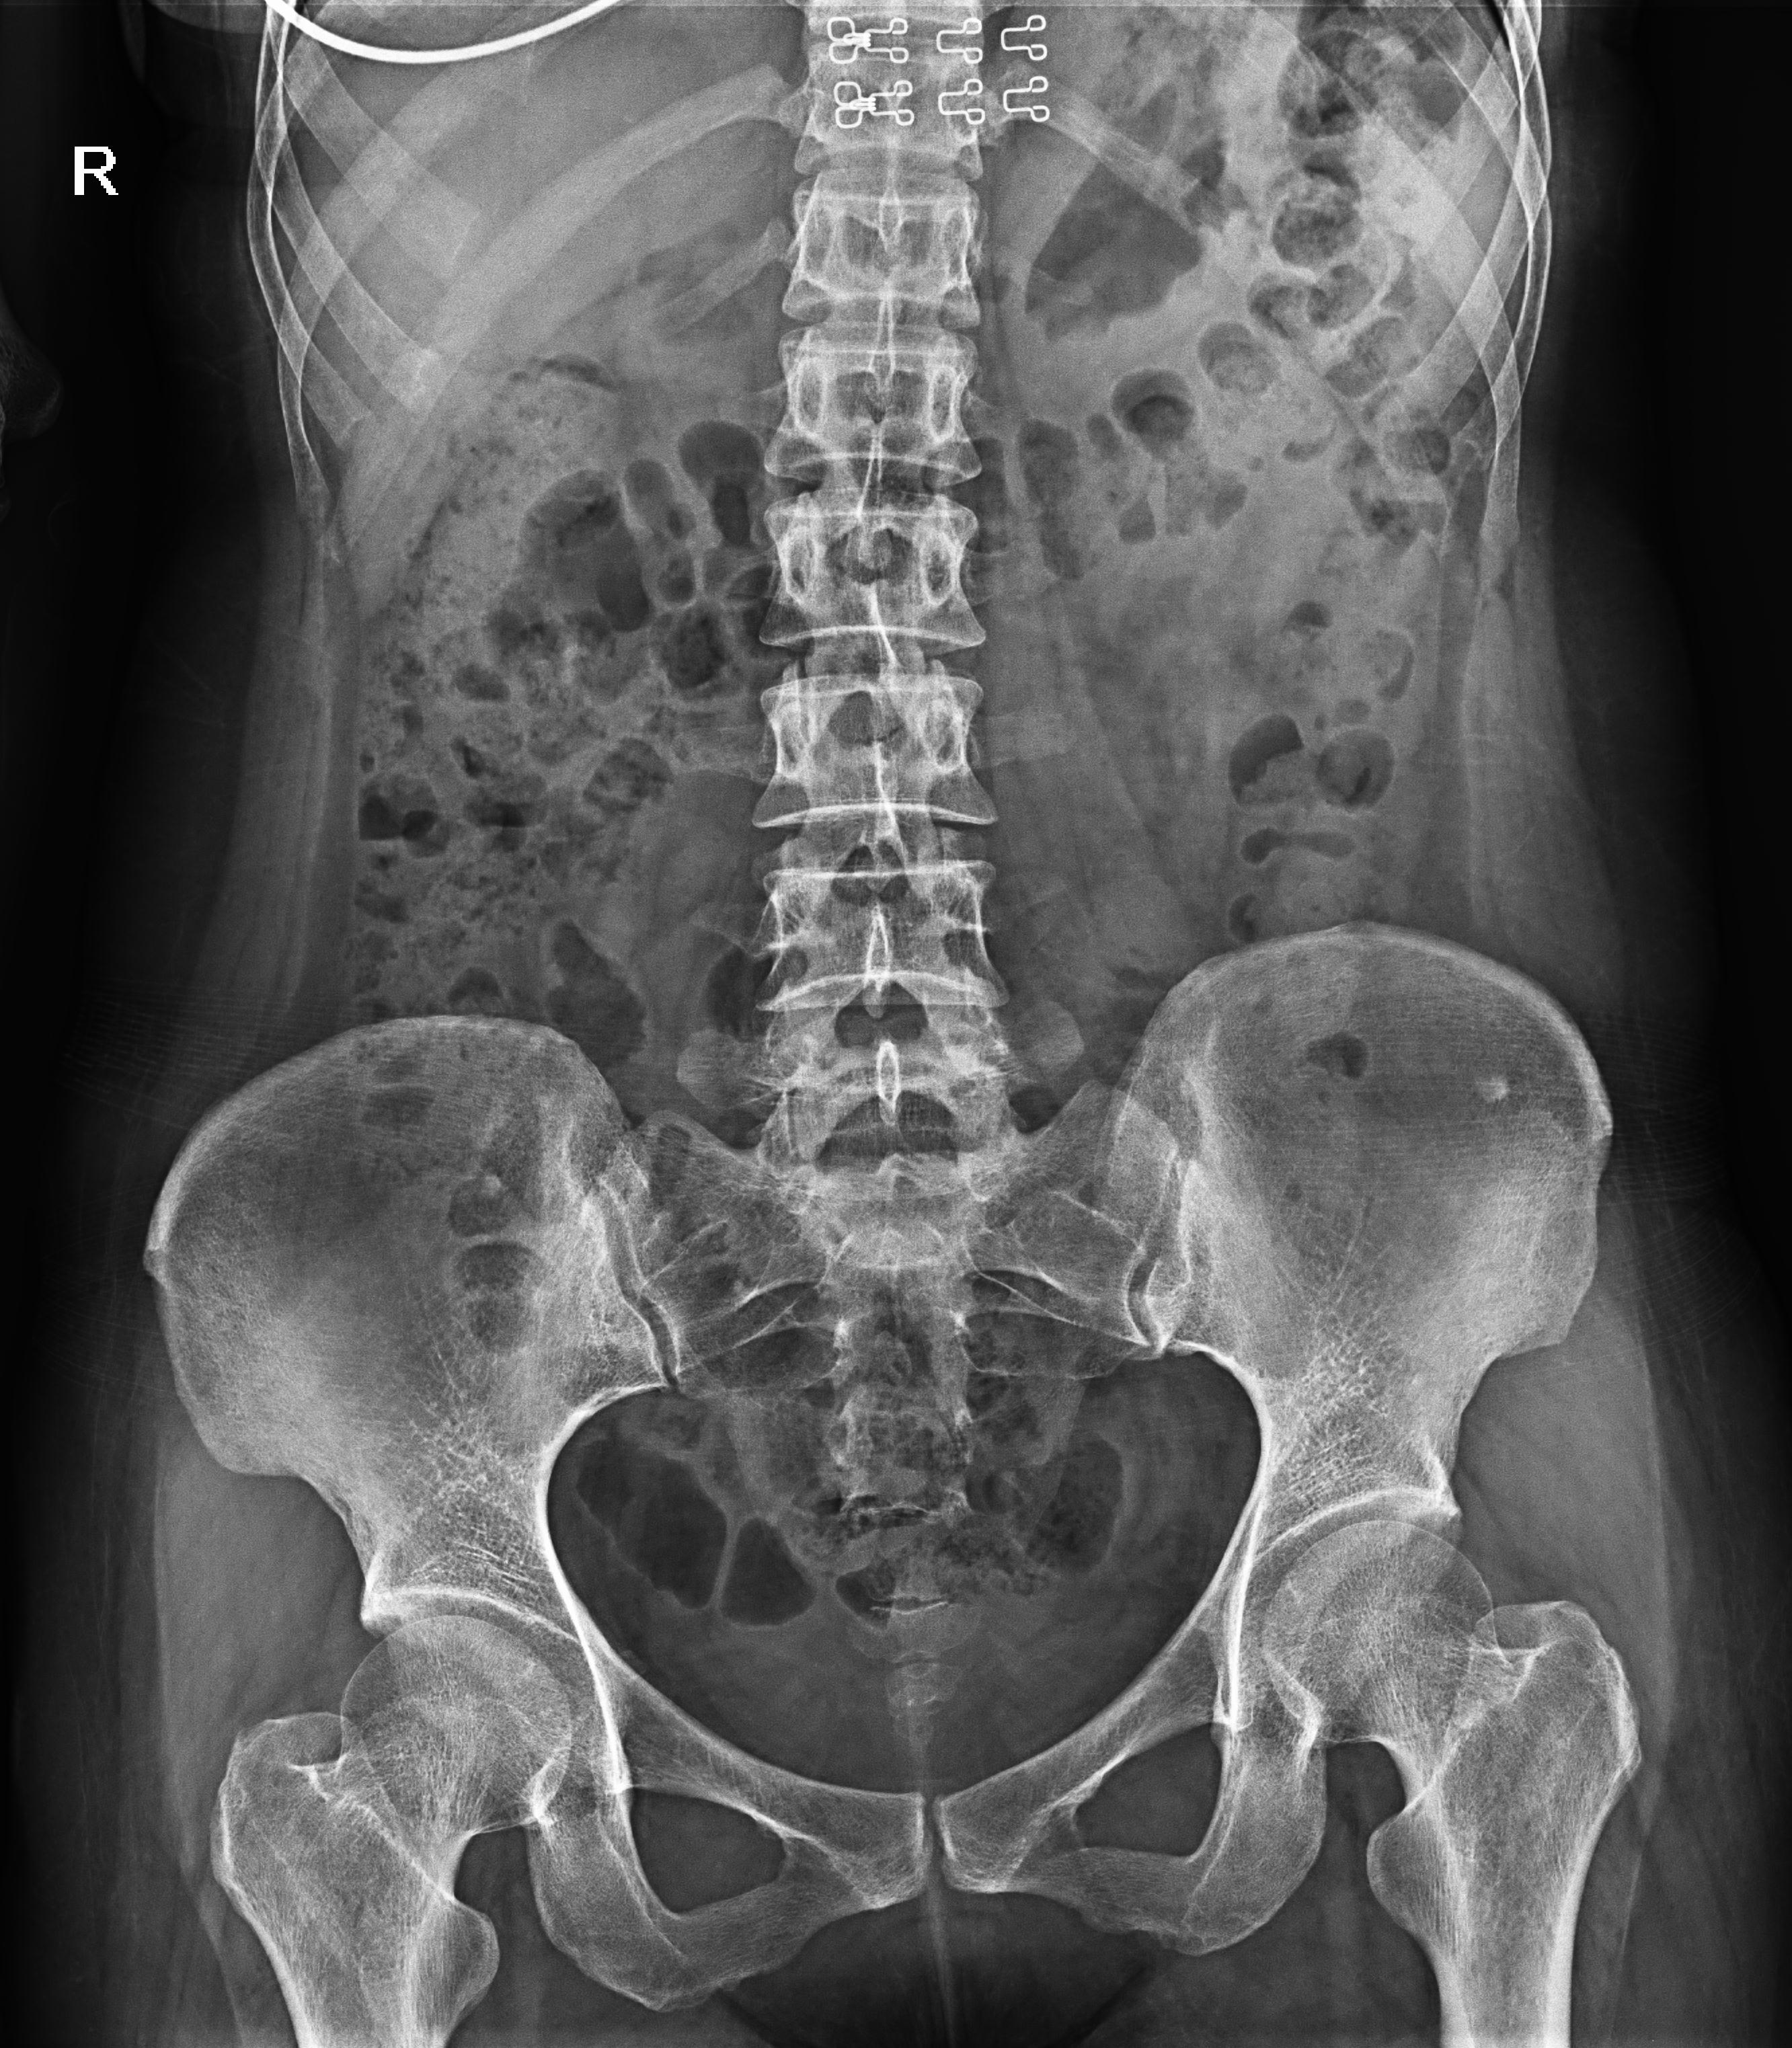

普利德醫療自主研發的新一代數字化X線透視攝影系統,可應用于DR攝影、數字透視、數字造影以及可視化精準DR拍片等多種臨床X線檢查領域。

● 17*17英寸的超高清像素動態平板探測器,更大的視野范圍,無需移動即可觀察整個動態過程,避免拖尾、噪聲對圖像的影響;

● 高效動態平板技術,圖像不會有幾何畸變,提供高分辨率和精確的圖像,為醫生臨床診斷提供精準依據;

● 最高幀速可達30幀/秒,動態采集清晰流暢,避免漏診、誤診情況的發生;

● 在可視過程或回放過程中,如發現疑似病灶,可進行毫秒級高清點片,隨時抓取單幀圖像,精準捕抓病灶。